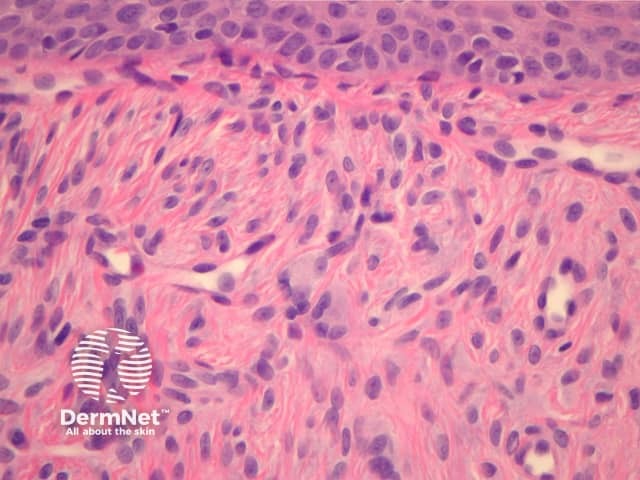

Angiofibromas cause a dome-shaped mass in the superficial dermis (figure 1). The overlying epidermis is uninvolved but may be atrophic. The lesion is characterized by a proliferation of stellate and spindled cells around blood vessels (figure 2). There are coarse concentric collagen bundles (figures 1, 2). Comparing the density of the collagen of the lesion with the surrounding dermis, which should be looser or elastotically damaged, can be a helpful diagnostic clue. Occasionally, a sparse inflammatory cell infiltrate of lymphocytes is present.

Figure 2